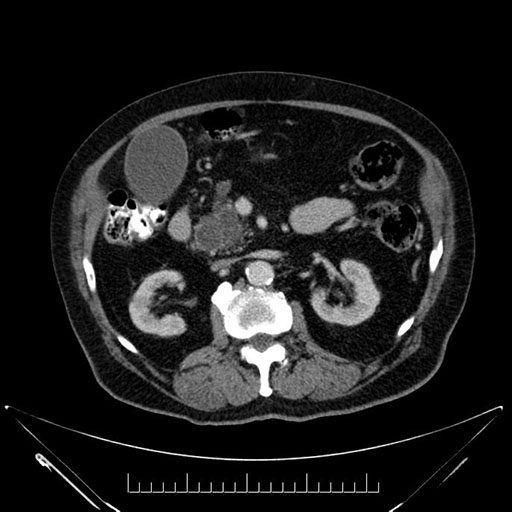

Imaging Analysis

Look through the patient's CT scan to identify any areas of concern for the necessary procedure.

Based on your CT findings, which issue(s) would give reason for "planned slowing down moment(s)" in this case?

Considering a standard Whipple procedure, what step(s) of the operation would you do differently in this case?